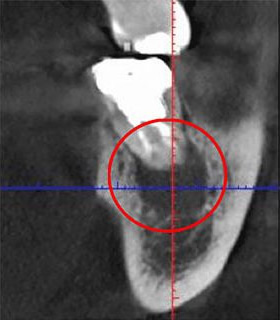

次の写真をご覧ください。同じ部位をCTとレントゲンで撮影したものですが、違いは歴然です。

CT撮影(左)では、暗い領域が確認できます。この部分には、炎症が起きています。しかし、レントゲン写真では異常は見られません。もしレントゲンでしか検査していなかったら、この炎症は見過ごされていました。最悪の場合、抜歯となっていたかもしれません。

当院では、このような事態を回避するため、CTを使用して検査を行います。